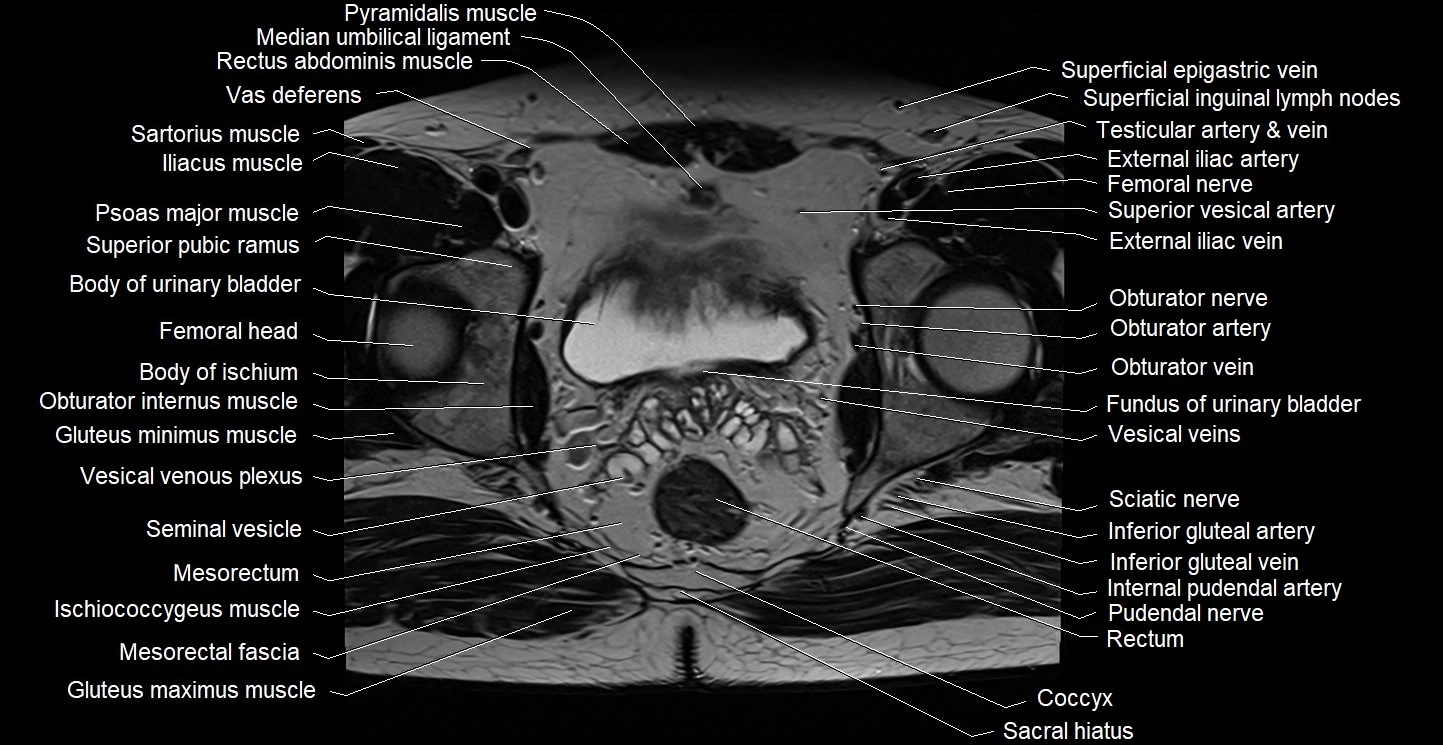

- Body of ischium

- Body of urinary bladder

- Fundus of urinary bladder

- Gluteus maximus muscle

- Gluteus minimus muscle

- Iliococcygeus muscle

- Inferior gluteal artery

- Inferior gluteal vein

- Internal pudendal artery

- Internal pudendal vein

- Ischiococcygeus muscle

- Median umbilical ligament

- Mesorectal fascia

- Mesorectum

- Pudendal nerve

- Pyramidal muscle (pyramidalis muscle)

- Rectum

- Sacral hiatus

- Sacral plexus

- Sciatic nerve

- Seminal vesicle

- Vesical veins

- Vesical venous plexus